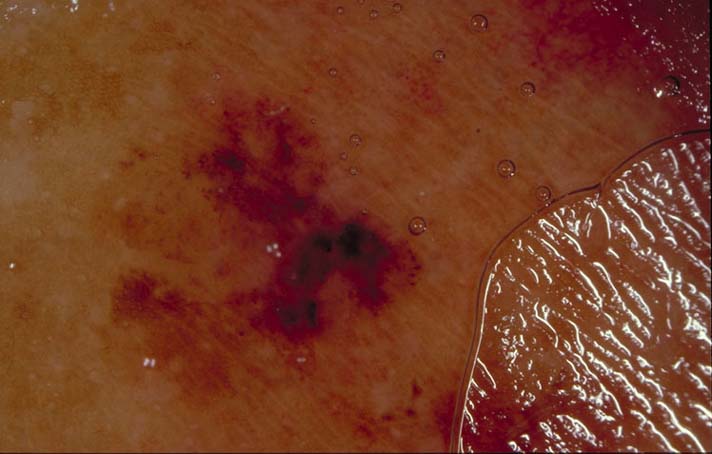

| 115 "diagnosis.char"="" "comment.char"="" "features.char"="" | "diagnosis.char"="Subungual hematoma" "breslow_depth.float"="0" "comment.char"="Red blue lacunes indicate the presence of blood. It’s very rare for melanoma to start on the side of the nail." "features.char"="" |  |  |